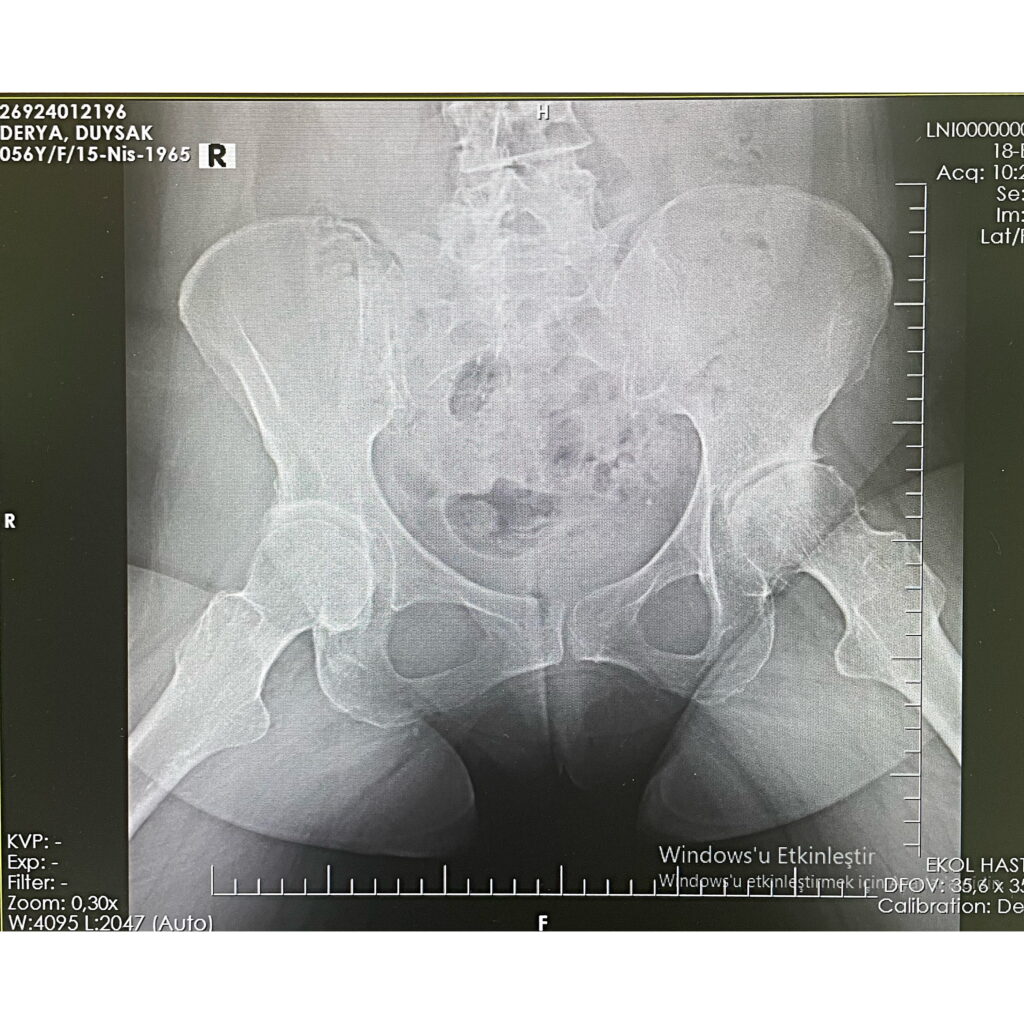

D.D.